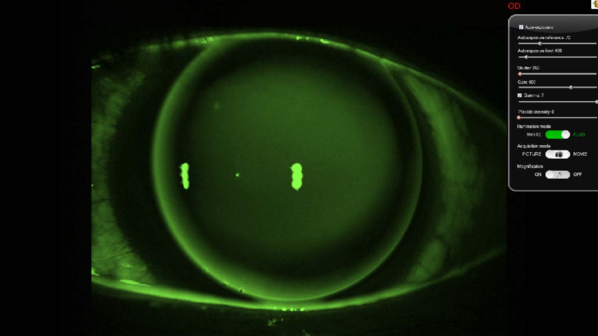

Antares眼表综合分析诊断系统是CSO公司全新推出的全功能的眼表综合分析诊断。采用白色LED光源、红外LED光源以及钴蓝色光源结合,对眼表疾病进行综合检查。根据干眼以及眼表疾病的检查需求,Sirius-Antares设计了多项检查功能,这包含角膜地形图、瞳孔计、睑板腺拍摄、泪液稳定度分析、泪河高度、眼红拍摄、脂质层分析等。

· 眼表荧光染色检查

角膜染色拍摄